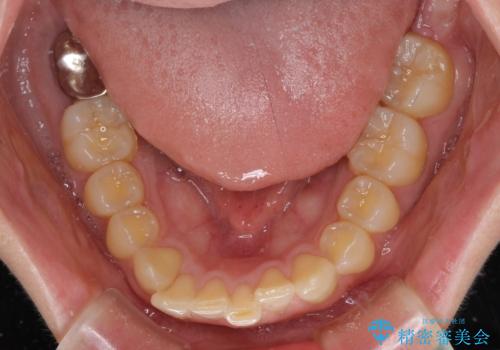

- 上顎前歯の前方に傾斜した咬み合わせを気にして来院された患者様です。

奥歯の咬み合わせを見ると、上顎が下顎に対して相対的に前方にありました。

深い咬み合わせを改善するためには、上顎臼歯を後方に移動させつつ、下顎の小臼歯を直立させる必要があります。